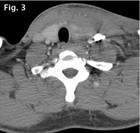

However, a large hematoma of the soft tissue expanding to the hypopharynx could be observed. The swelling impaired the differentiation of the Mm. sternohyoideus, sternothyroideus, thyrohyoideus, omohyoideus and left sternocleidomastoideus. Some muscle fibres of the latter seemed to be partially ruptured. The centre line was significantly displaced to the right, but without tracheal compression (Fig. 3).